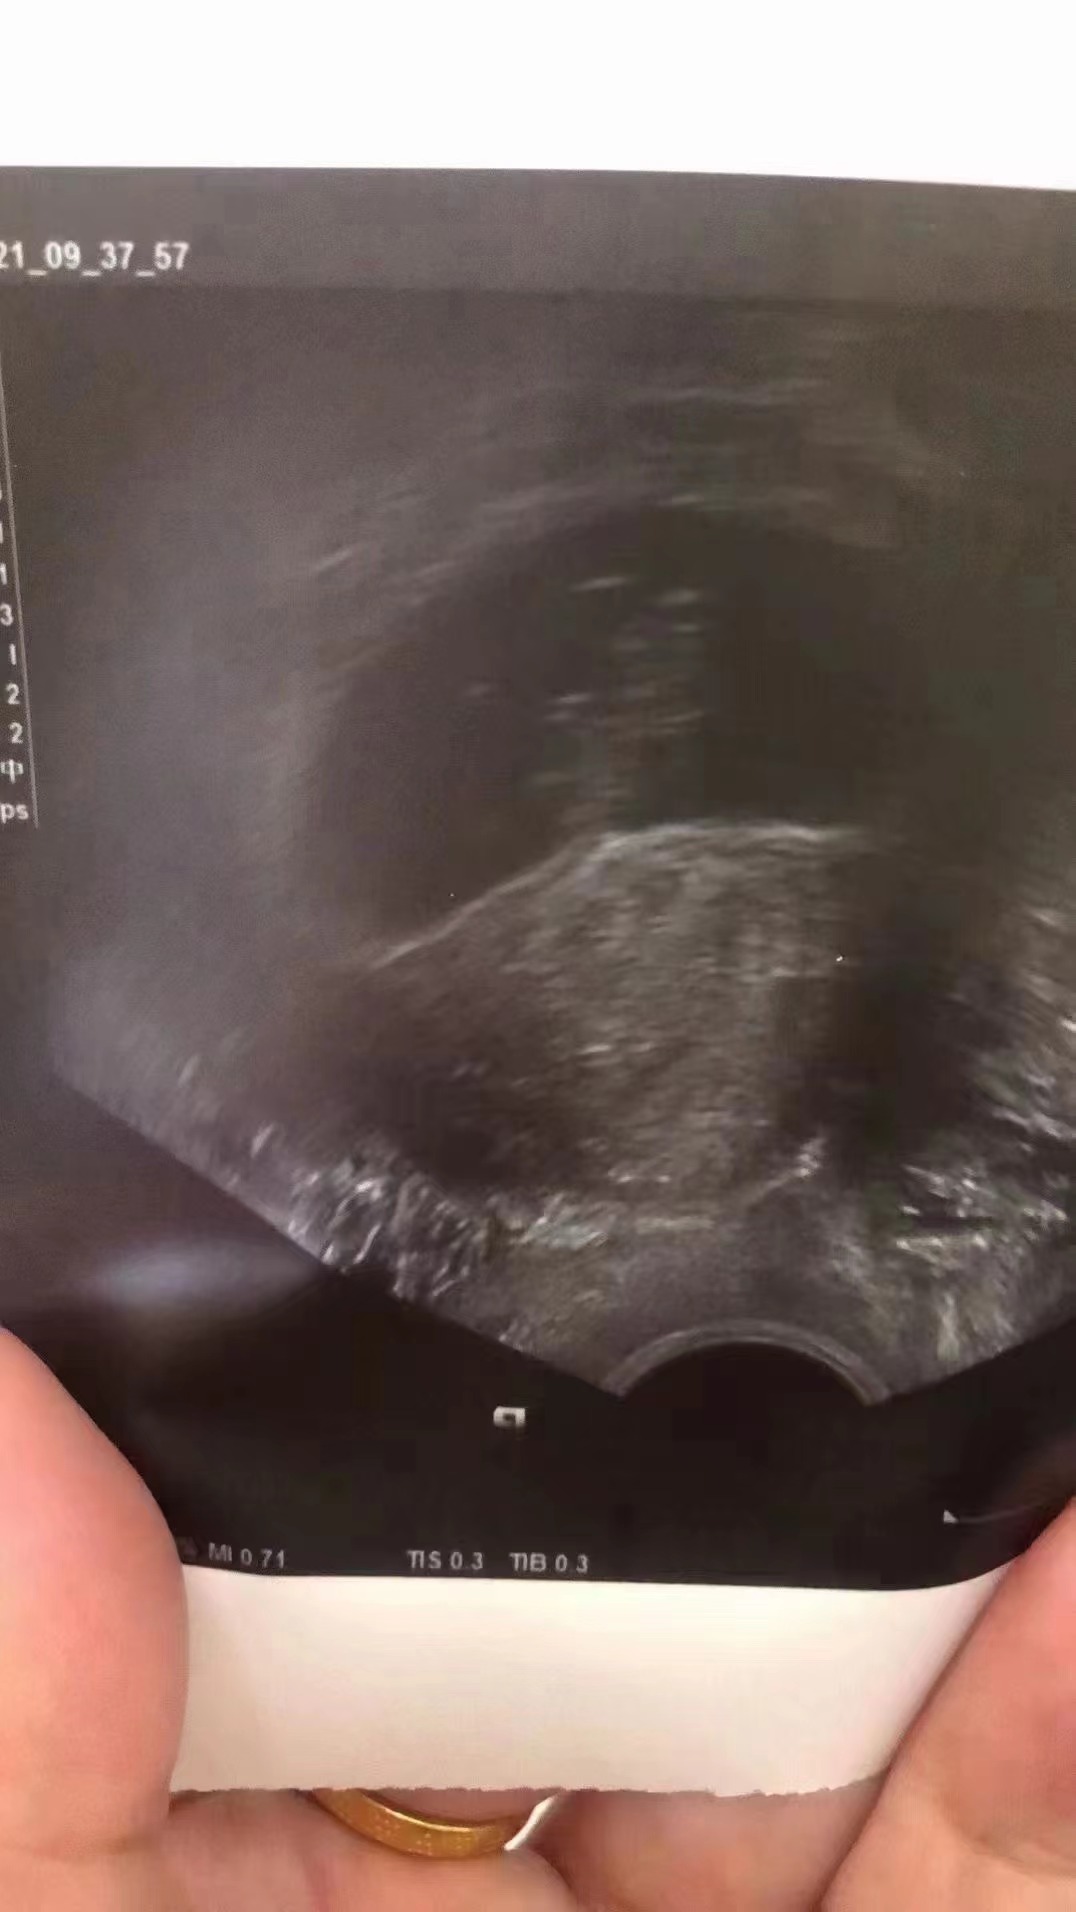

众所周知,PCOS是不孕症最常见的原因之一。曹女士和她的丈夫很快就陷入在生殖治疗的历程中。曹女士说“当我第一次被诊断出来时,医生确实提到我可能自然怀孕很困难,这倒是让我难受了一阵儿,但当时还小,也没想要孩子,就这么听之任之。后来结婚了,准备要孩子的时候,就去看医生,说有这个PCOS,就一边治疗一边尝试怀孕,大概有一年时间吧。治疗期间我们做了很多遍预约、吃药、注射、抽血和阴道超声检查等事情。我每周去医院最少3次,都是大早上6点就出门了,现在想起来确实心酸。”

曹女士的爱人说:“我们尝试了大概一年,之后又做了试管婴儿,之后我爱人怀孕的时候。移植14天后我们在家验了早孕,结果是阳性的。3天后,我们又到医院验血,HCG就翻倍了,然后一周后又进行了一次检查,再一周后又查了B超。虽然怀孕40周是很长的,但我们知道怀上的时候一次次都是很兴奋的!有时候,我们简直不敢相信这是真的。”